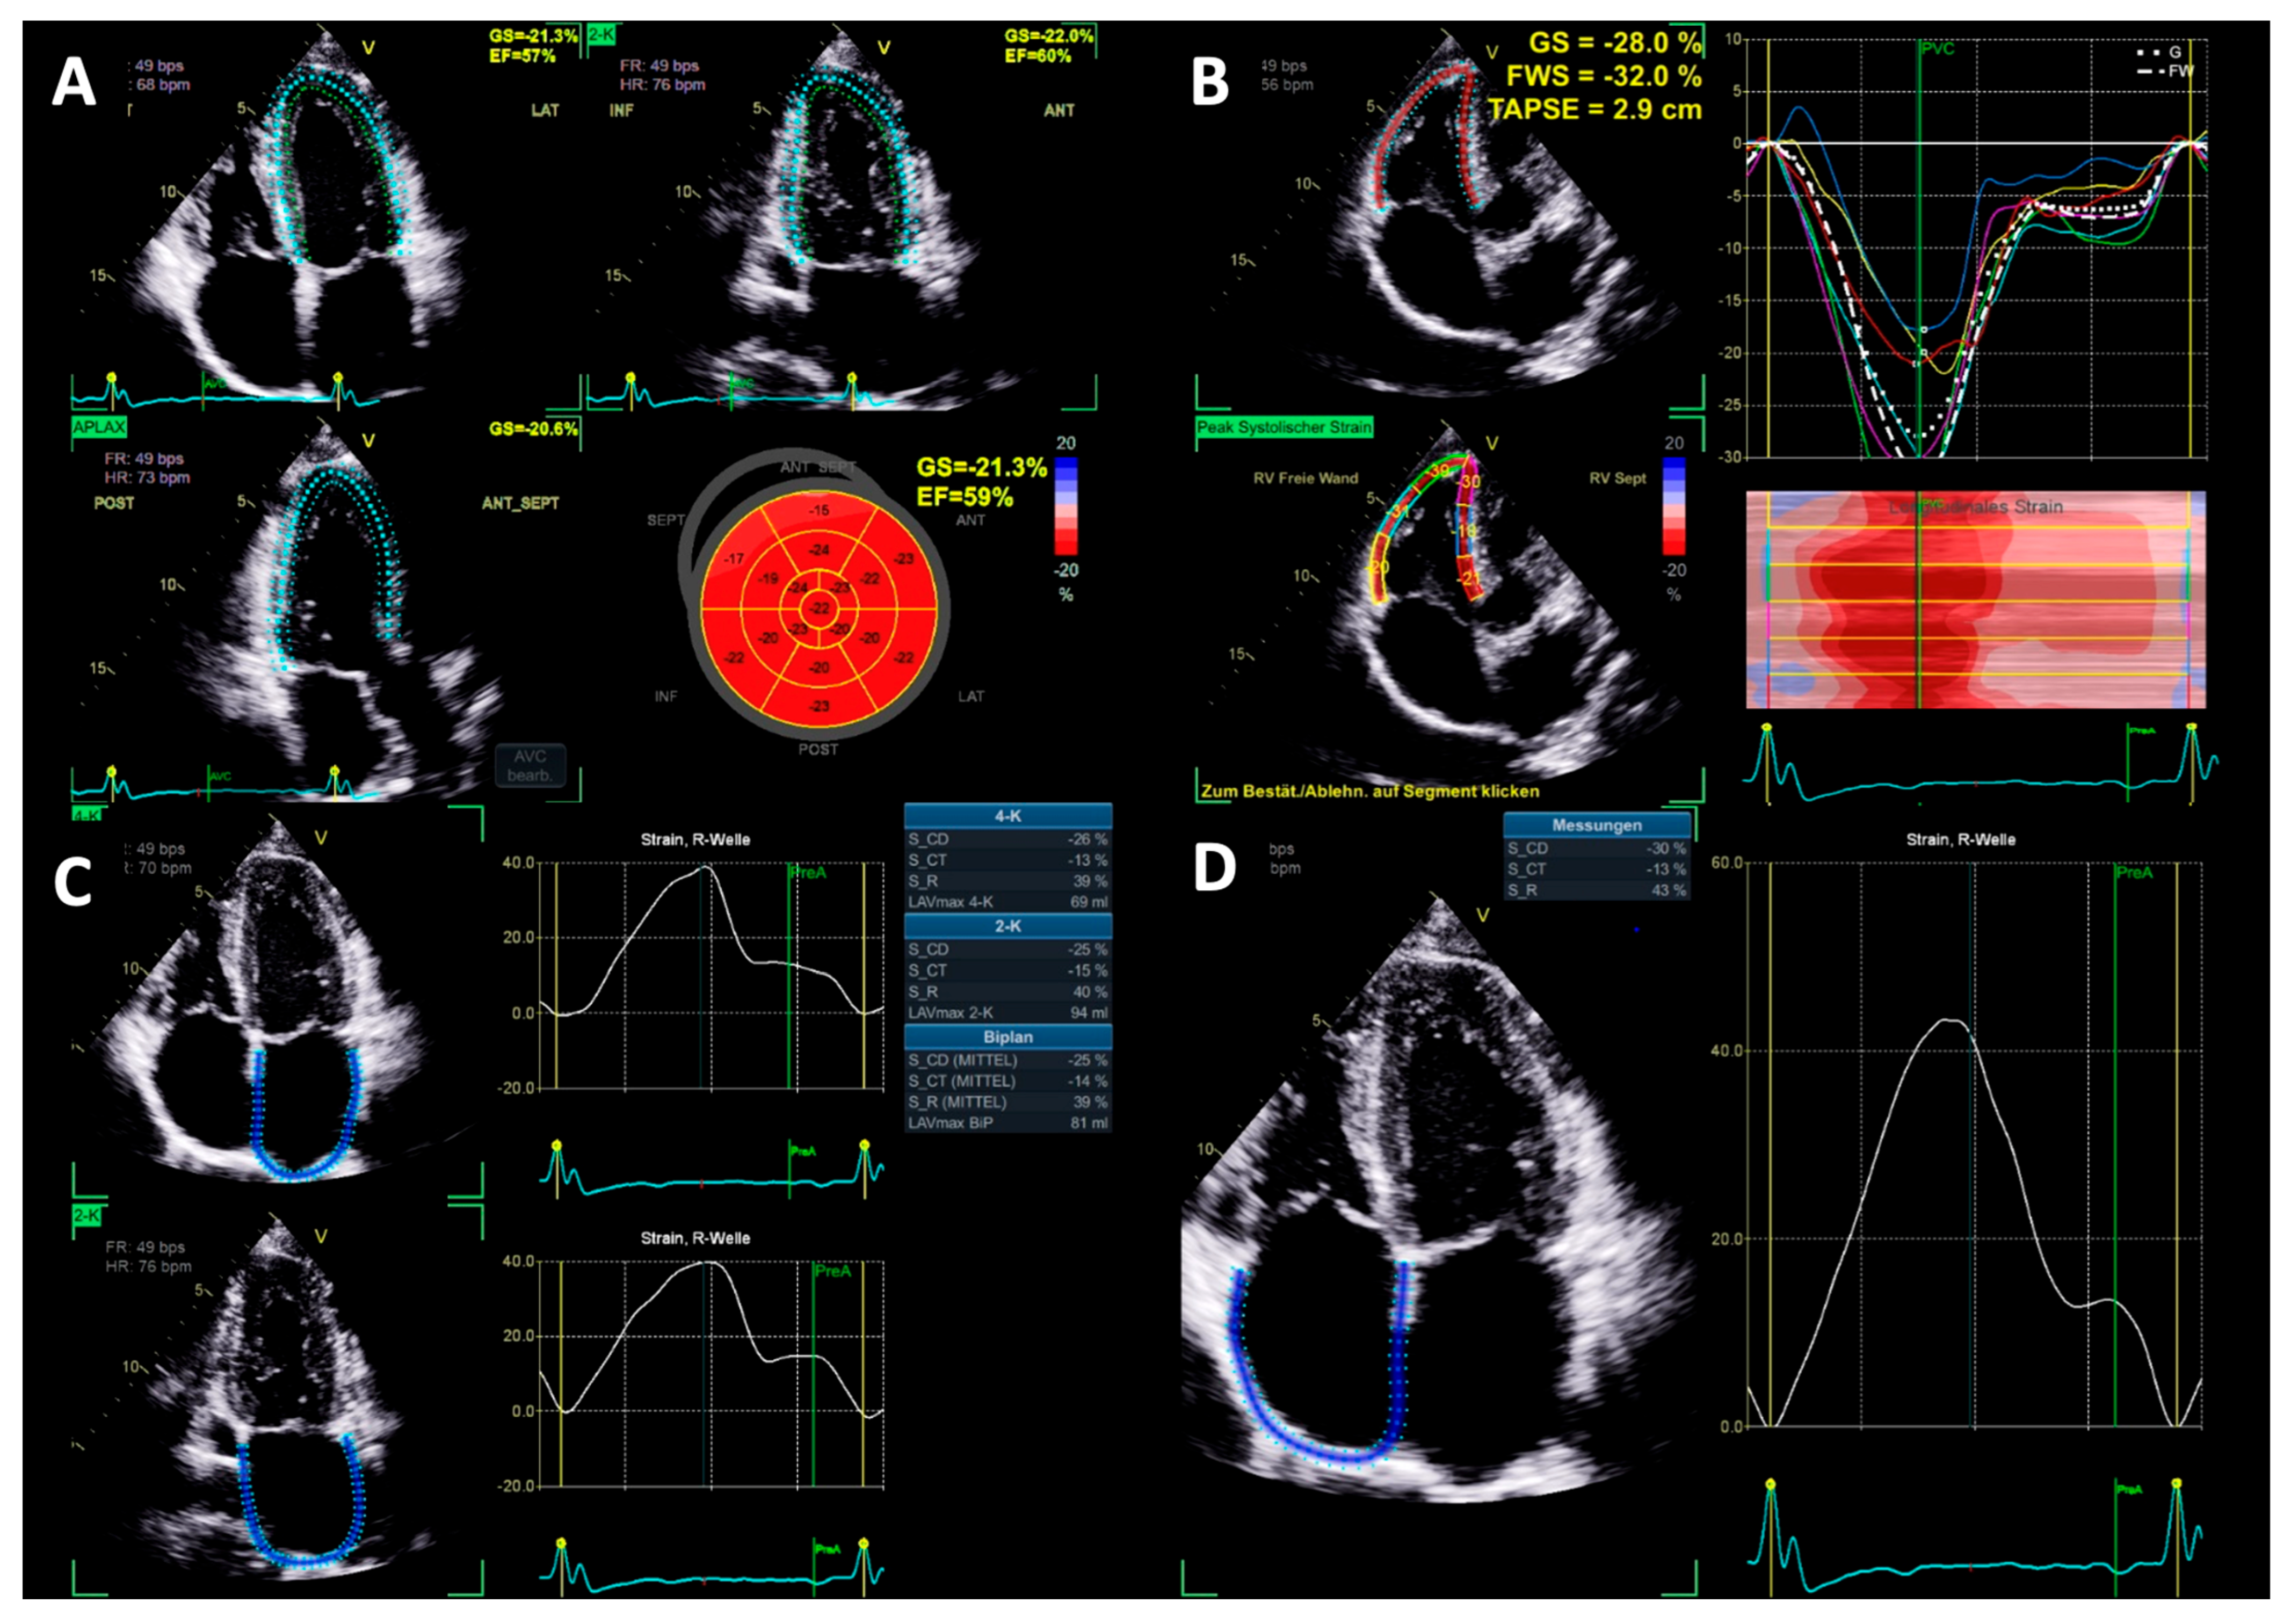

2.4. Left Heart Morphology and Function

2.5. Right Heart Morphology and Function

4.3. Changes in Myocardial Deformation

4.4. Atrial Function